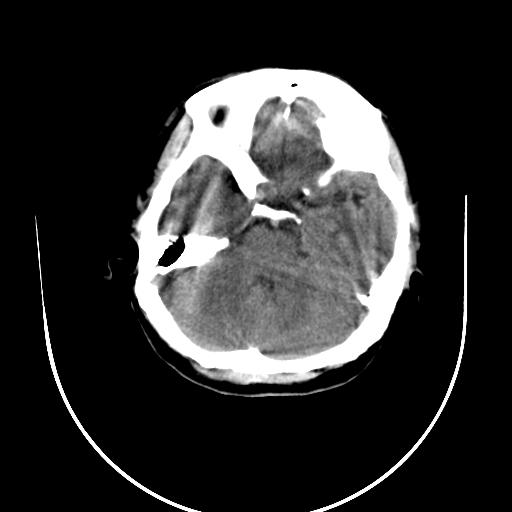

标题: CT10010:女/24岁,癫痫一周,发作时间不固定. [打印本页]

标题: CT10010:女/24岁,癫痫一周,发作时间不固定.

右侧额叶正常吗?

右额叶镰旁饱满.

右侧外侧沟?中央沟?可能有问题,不知以前有没有癫痫过,最好是增强下,排除局部血管畸形等病变

倒数第6幅图中线结构有点偏,而侧脑室额角未见异常,可结合增强扫描。